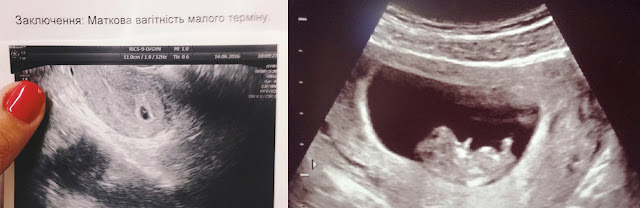

Вот тогда наш год и поделился на "до" и "после". Проверив у врача наши подозрения, мы с Мишей узнали, что теперь мы не одни и похоже пора готовиться с приятным переменам. Нашему малышу тогда было всего 5 недель и он был размером с зернышко :)

Июль получился насыщенный поездками. Вначале Гданск, Сопот, Гдыня и холодное Балтийское море. Мы впервые поехали в эту часть Польши. Мыслями конечно хотелось отдохнуть, гулять и наслаждаться морем, но на деле оказалось, что мне хочется только спать - такими были первые признаки моего нового "положения". Стоит сказать, что не было ни токсикоза, ни каких-либо других физических сложностей, я просто "впала в глубокую спячку" и мне было все равно - на море мы или дома. Могла спать часами днем, при этом так же крепко по 8-10 часов ночью :)